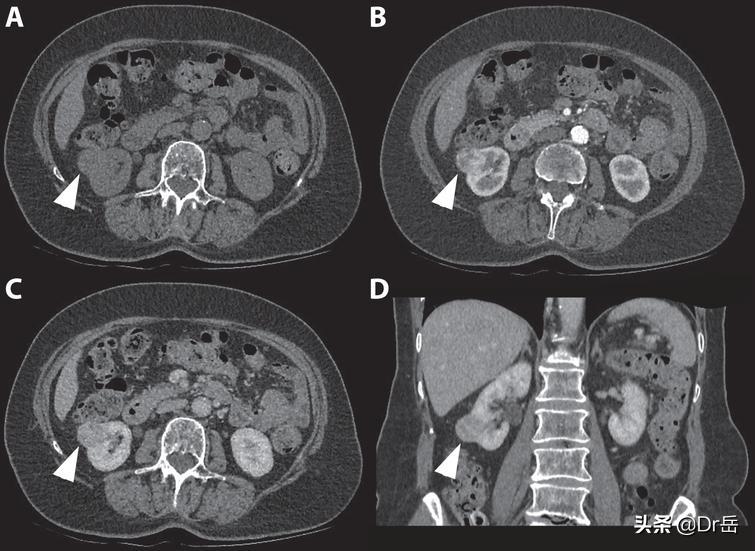

CT:肾癌肺转移灶

比较可靠的研究表明,转移性肾癌做手术是对患者有益的,能够改善患者的生存质量,有可能能够提高生存期。手术切除的目标主要有两个,一个是原发灶,也就是将患癌的肾切除;二是对肾癌转移灶的切除,比如肾癌的肺转移,但是转移灶的切除只限于孤立性的转移,如果是多发转移,手术就没有太大的意义了。

- 如果患者是孤立性转移灶,而且对免疫、靶向治疗反应差的情况下,可以进行转移灶的切除。转移灶切除的同时也是要对原发灶进行切除的。